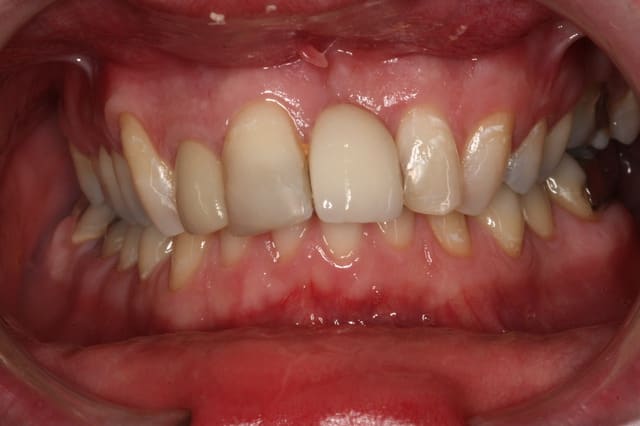

Bon, ton cas est terminé, en voici un dans le mêm style.

Jeune patient, 25 ans, n'aime pas son sourire.

Tu fais quoi ?

Arrivant sur le tard pour cause de vacances (ah la Corse!!! quel pied!), j'ai l'avantage d'avoir vu l'avant et l'après, plutôt d'accord avec Ceramik pour traitement global mais aussi avec Marcus pour respecter le choix du patient.

Pourtant a y regarder de plus prés j'ai la sensation d'une amélioration de la qualité des soins précédemment réalisés chez ta patiente, Maz, mais pas d'une amélioration du sourire, juste un peu de Rimmel quoi ! donc tout est question de langage et d'appréciation et d'expérience perso, si dans ton cas tu as réalisé le souhait exprimé de la patiente, alors tu as tout bon.

Céramik: la 21 c'est bridge à ailette? si oui, y reste quoi comme os en dessous. Elle a vraiment 25 ans? Il y aura (y a eu puisque déjà traité je suppose) expansion maxillaire = 9 à 12 mois d'ortho puis traitement ceram pour qui veut je présume.